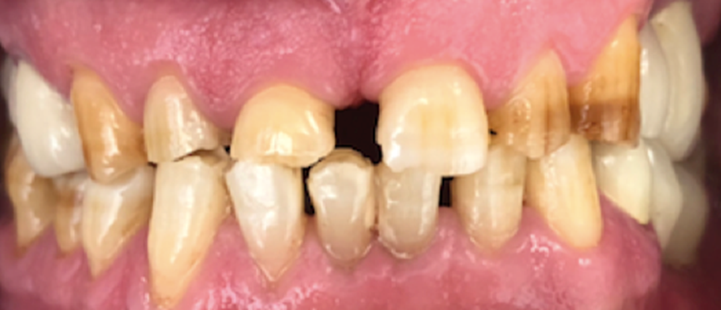

Resident Case Photos

The following are before and after photos of dental patients who have been treated by the residents at NYC Health + Hospitals/South Brooklyn Health. To apply to the program visit the Dental GPR Page and click on Application Information.

Veneers